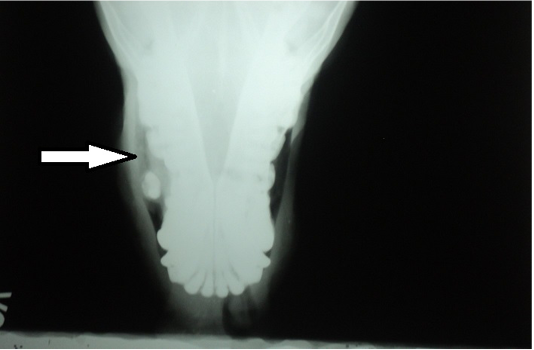

Figure 2

Radiography of rostral view revealing a radio opaque mass (arrow) in the right nostril